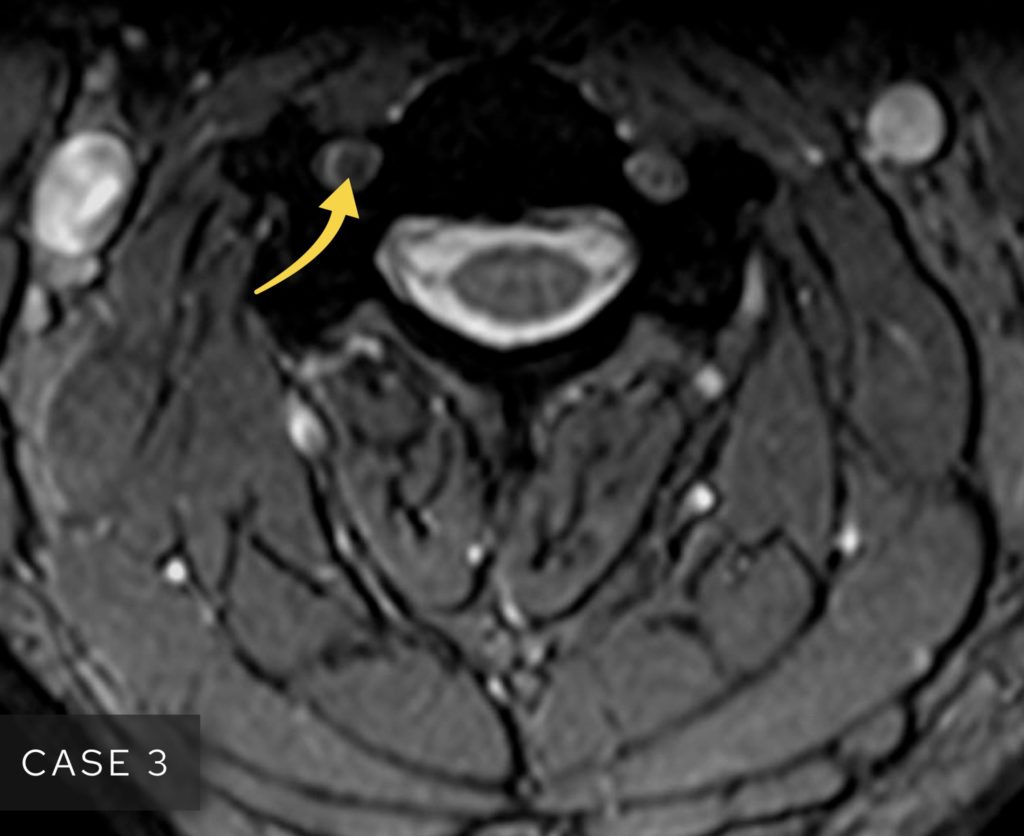

The three hepatic veins look a bit like ‘crow’s feet’ and can be easily distinguished as right, middle and left.

The three hepatic veins look like ‘crow’s feet’ heading towards the inferior vena cava